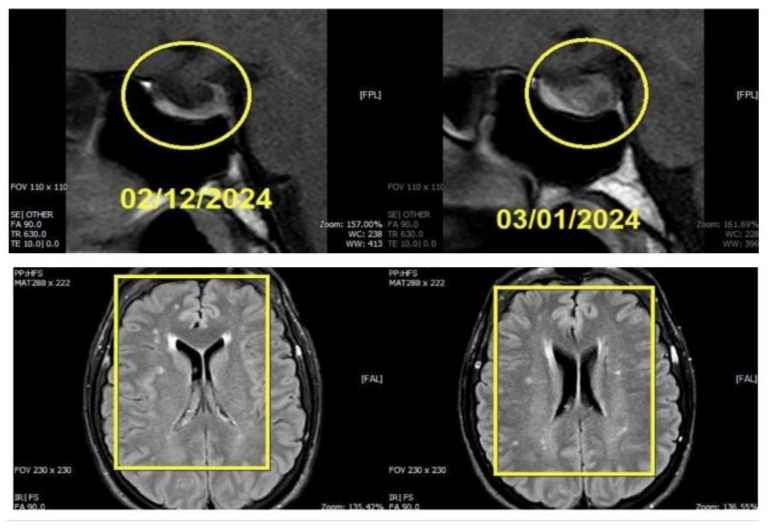

The patient chose medicinal care over surgical intervention. Sandostatin LAR (octreotide), a somatostatin analog, was prescribed to her with a steady increase in dosage. IGF-1 levels gradually decreased in follow-up lab tests, suggesting a successful course of treatment. A regressive phase of the disease was suggested by repeat MRI scans that showed cystic degeneration and a decrease in the size of the pituitary adenoma.

Pituitary MRI revealed an enlarged pituitary gland due to a welldefined ovoid lesion predominantly involving the left lateral wing of the anterior lobe (adenohypophysis), measuring 14 × 12 × 9 mm. The lesion exhibited a heterogeneous texture, with mixed high and low signals on T2-weighted imaging (T2WI) and heterogeneous isointense to low signal on T1-weighted imaging (T1WI). Post-contrast series demonstrated faint heterogeneous enhancement, which was less than that of the adjacent normal pituitary parenchyma. The superior surface of the pituitary gland appeared elevated and convex, with mild rightward deviation of the pituitary stalk.

From February 6, 2024, the patient was initiated on Sandostatin LAR 20 mg administered intramuscularly (I/M) at 28-day intervals for a duration of three months, concluding on April 4, 2024. Following the second dose, laboratory investigations revealed a growth hormone (GH) level of 1908.00 pg/mL and an insulin-like growth factor 1 (IGF-1, Somatomedin-C) level of 310.60 ng/mL.

Given the persistence of elevated IGF-1 levels, the treatment regimen was escalated to Sandostatin LAR 30 mg, administered from May 5 to July 4, 2024, at the same 28-day intervals. A laboratory evaluation on June 28, 2024, demonstrated a further reduction in IGF-1 to 292.90 ng/mL.

Subsequently, the dosage was increased to Sandostatin LAR 40 mg, administered from August 5 to October 4, 2024, with IGF-1 reassessed on August 9, showing a decrease to 238.00 ng/mL. The patient continued on Sandostatin LAR 40 mg, and by November 9, 2024, IGF-1 had further declined to 120.00 ng/mL, achieving normalization.

The patient was followed up from January 2024 onwards after opting for medical therapy as a choice over surgery. Sandostatin LAR (Octreotide) was prescribed as part of the regimen, with gradual increase according to lab values and improvement clinically. The patient began with 20 mg (Feb–Apr 2024), 30 mg (May–July 2024), and 40 mg (Aug–Dec 2024). Lab work was done at intervals, with radiological follow-up regarding tumor size modification and response to therapy. Research indicates that somatostatin receptor ligands (SRL) like Octreotide can reduce tumor volume in 36–75% of cases [7].